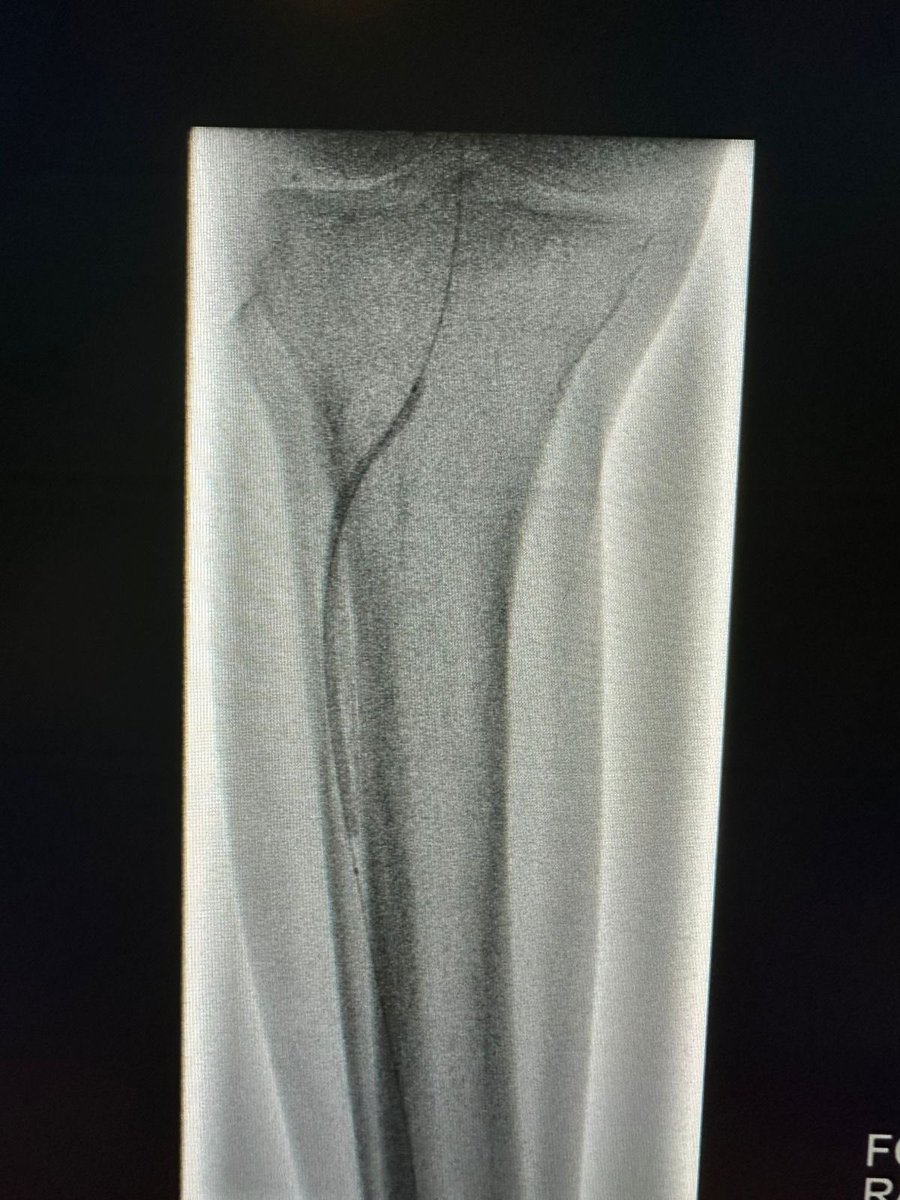

حالة من حالات نقص التروية الدموية الحاد مع وجود جرح غير ملتئم في القدم تم علاجها في وحدة #الأشعة_التداخلية بجامعة الملك سعود بالدخول من شرايين الفخذ والكاحل و إعادة فتح و توسيع الشرايين @ksumedicalcity @_KSU